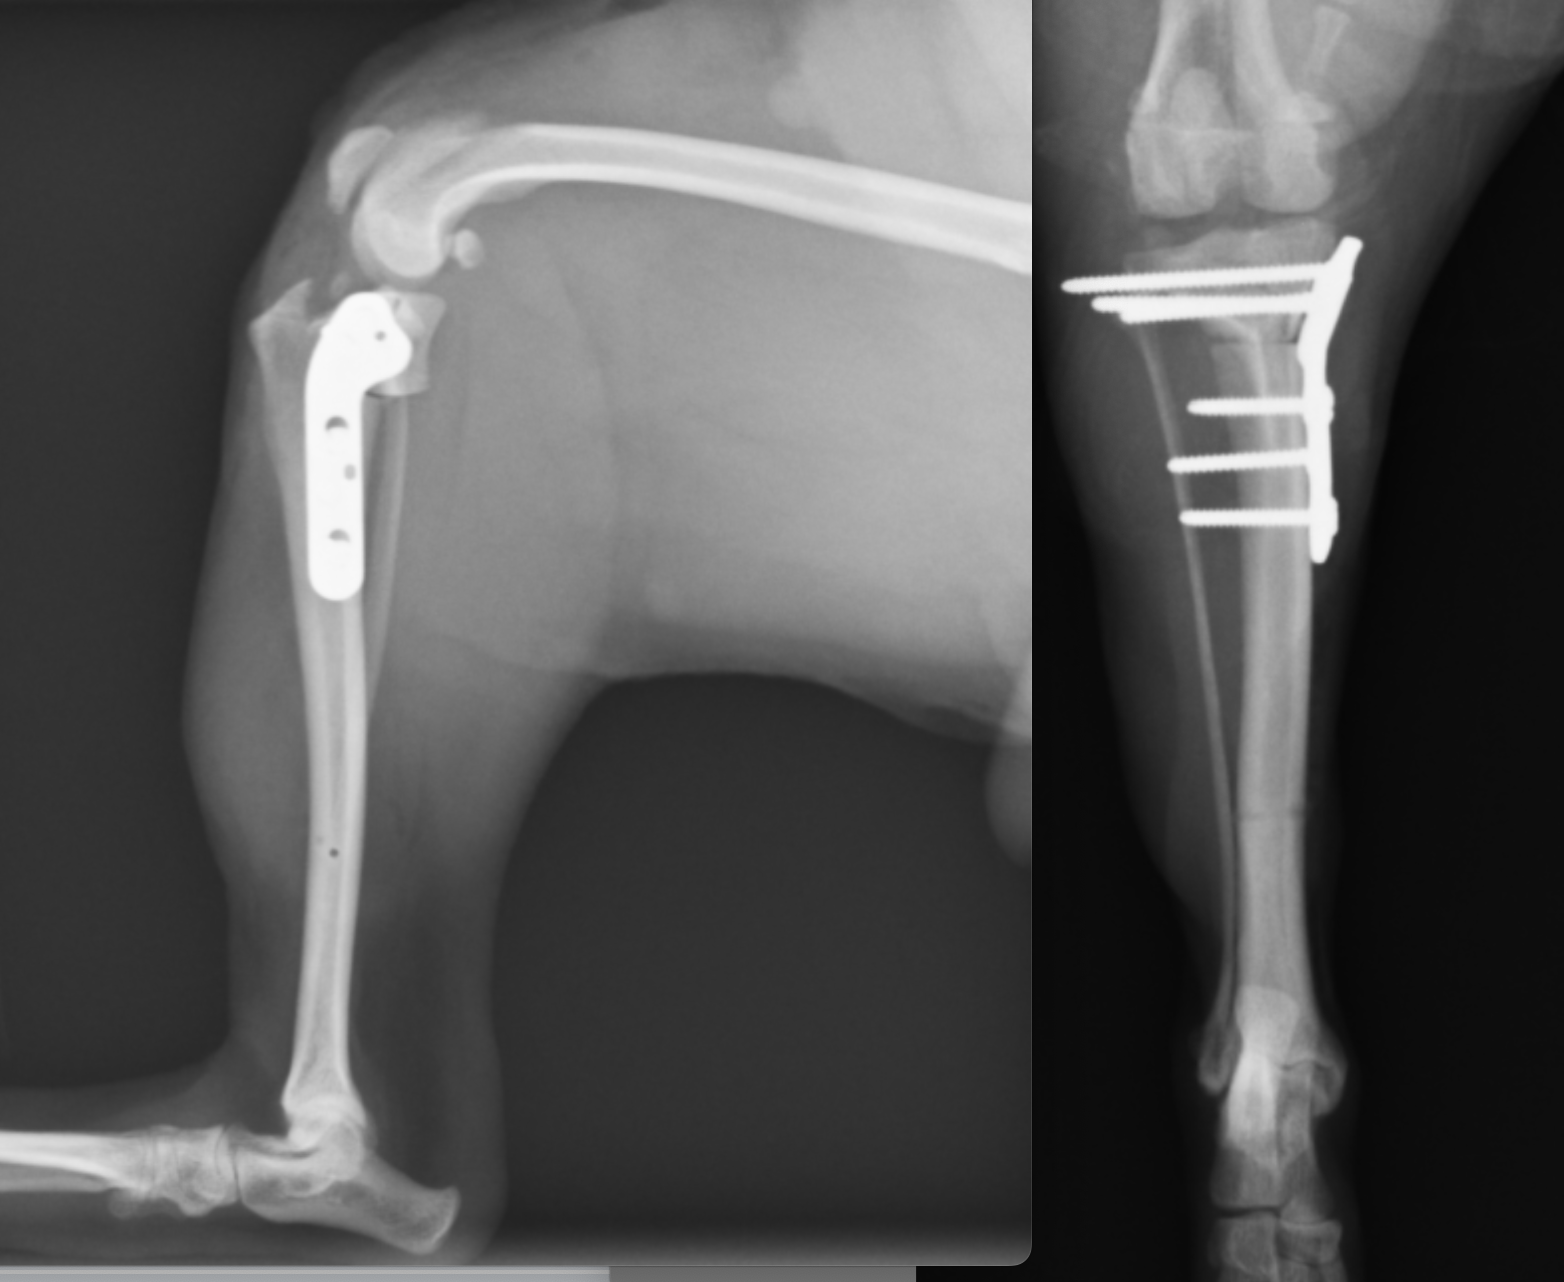

2025年6月22日開催の第110回日本獣医麻酔外科学会学術集会にて磯野がパテラ(膝蓋骨内方脱臼)の形態学的変化についての発表を行いました。CT画像をもとに脛骨の形態学的変化についてご説明させていただきました。

整形外科の雑誌であるVeterinary and Comparative Orthopaedics and Traumatologyに磯野の論文である「Tibial Torsion Malalignment in Small Dogs with Medial Patellar Luxation」が掲載されました。パテラ内方脱臼に対し、脛骨粗面と足根骨の捩れが関与しているをことを示し、その指標の一つを提言した内容になります。ご興味ある方はご覧ください。